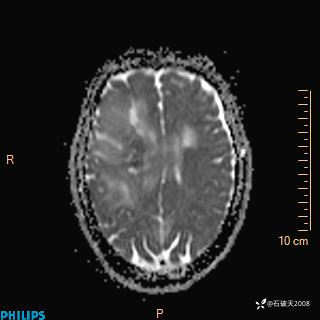

2024.2.21MR

ADC